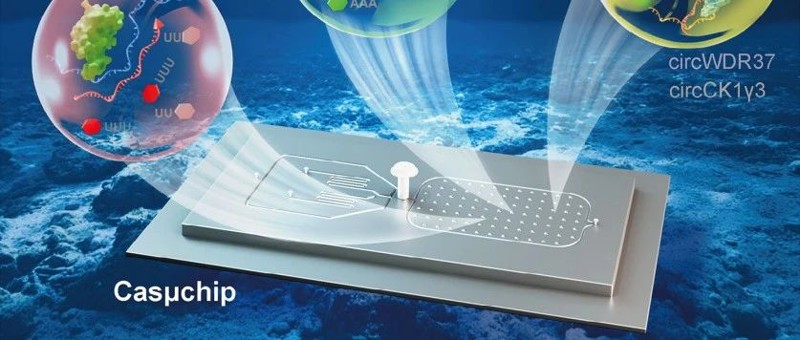

李敏、汪骅教授团队:开发新型检测平台助力结直肠癌无创早筛